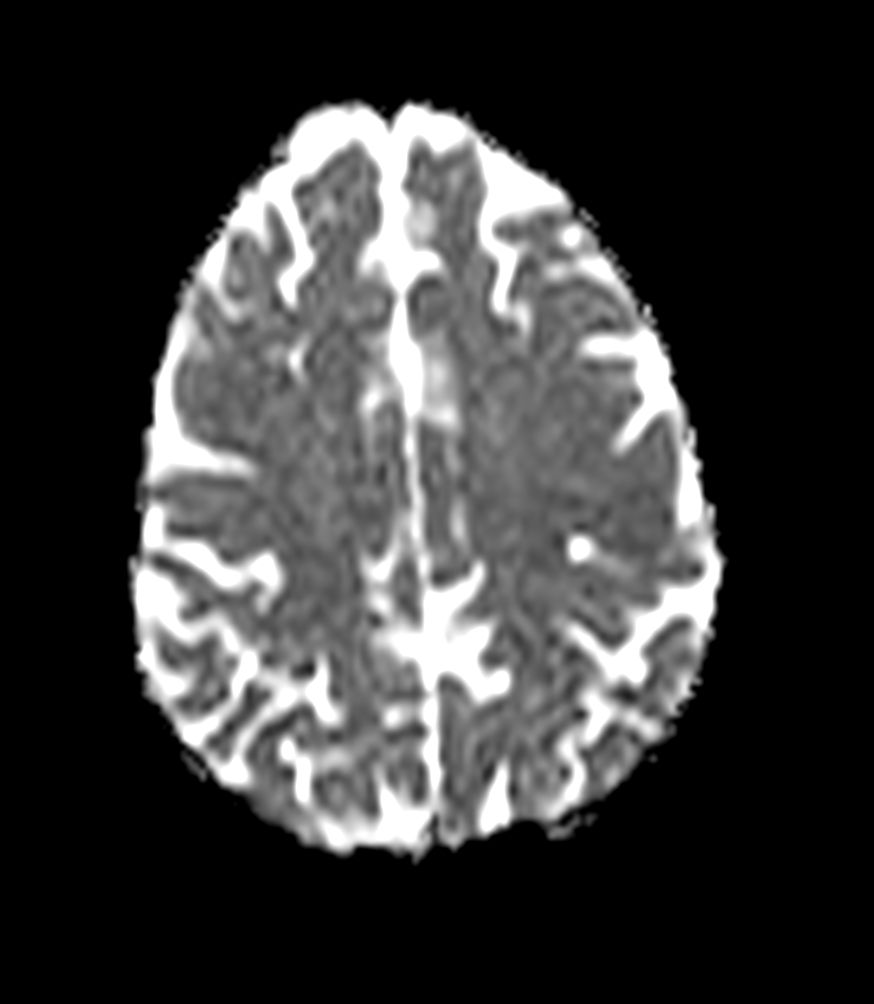

Female with one metastasis of pulmonary cancer underwent MRI simulation in the radiotherapy positioning mask on Ingenia MR-RT 1.5T before stereotactic radiation therapy with 25 Gy in 3 fractions.

Axial DWI (ADC)